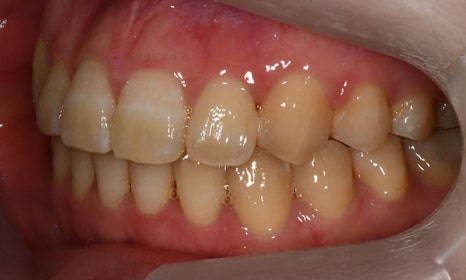

다음 케이스 역시 위 아래 치아의 중심선 차이가 있으며, 덧니 및 반대교합이 관찰되었습니다. 위 치아의 중심선도 얼굴의 중심선과 일치하지 않고 우측(사진 상 왼쪽)으로 틀어져 있었습니다. 본 환자는 발치를 하지 않고 치아를 뒤로 이동시켜서 치아의 중심선도 맞추고 얼굴의 중심선과도 맞추었습니다.

2020.1

교정 마무리 후 위 치아의 중심선은 얼굴의 중심선과 일치하였으며, 위 아래 치아의 중심선도 일치하였습니다.